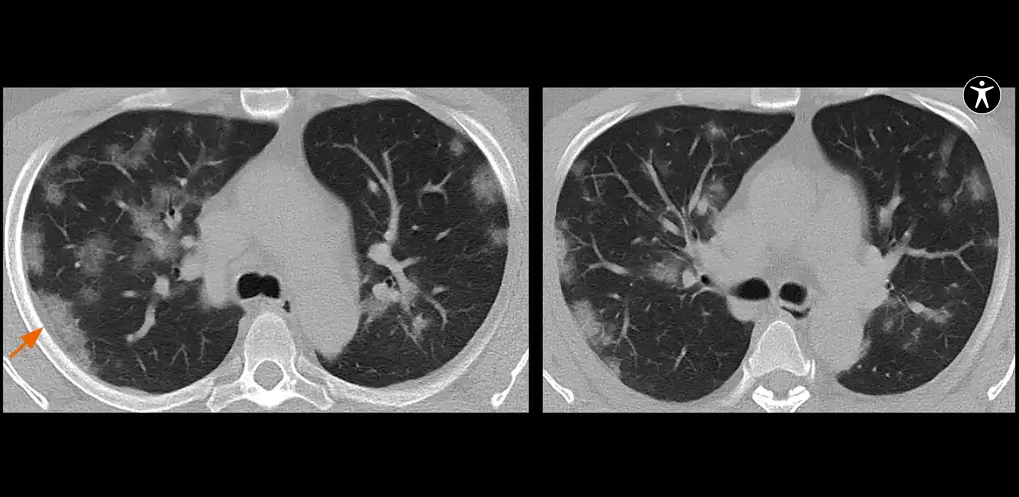

Quando o RX não esclarece completamente o quadro clínico ou há suspeita de complicações, a TC de alta resolução (TCAR) entra em cena. Ela permite observar com riqueza detalhes como espessamento septal, opacidades em vidro fosco, nódulos pulmonares, destruição alveolar e alterações brônquicas.

Com cortes finos e reconstruções multiplanares, é o exame de escolha para avaliar a extensão de uma fibrose, o padrão intersticial, ou confirmar/emergir lesões compatíveis com sequelas da COVID-19. Também auxilia no estadiamento de neoplasias pulmonares e investigações vasculares (angio-TC).

- Sequelas de COVID-19: vidro fosco, consolidações residuais, fibroses.